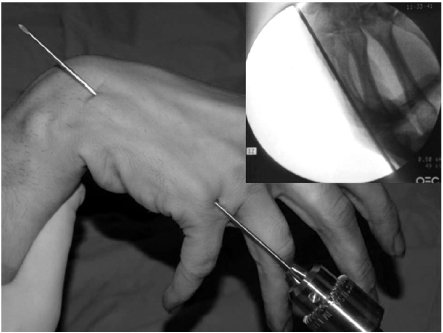

Fig. 1

1.6 mm K-wire is inserted from metacarpal head with metacarpophalangeal joint flexion for easy access to the medullary canal.

Fig. 2

When the wire tip passes fracture site and reaches to metacarpal base, wrist is bent maximum and further penetration is performed to proximal area.

The surgery was performed under general or regional anesthesia with image intensification, preferably with a tourniquet on the upper arm. Under the fluoroscopy, closed reduction of the metacarpal fracture was achieved by manipulation, and 1.6 mm K-wire was inserted from metacarpal head with MP joint flexion for easy access to the medullary canal (Fig. 1). When the wire tip passed fracture site and reach to metacarpal base, wrist was bent maximum and further penetration was performed to proximal area (Fig. 2). The distal end of K-wire was pulled up until its tip end lay within the metacarpal head (Fig. 3). Penetrated proximal part of wire was bent over, cut and buried under the skin (Fig. 4). During this procedure, any rotation of fracture was carefully checked with passive flexion and extension motion of the finger. Ulnar gutter splint was applied for rotational stability and pain relief. It was changed to extension block splint and encouraged motion exercise from postoperatively 1 week. After fracture healing, the wire was removed with local anesthesia in the outpatient department in all cases. We make small skin incision at proximal bended wire and pull out that with local anesthesia.